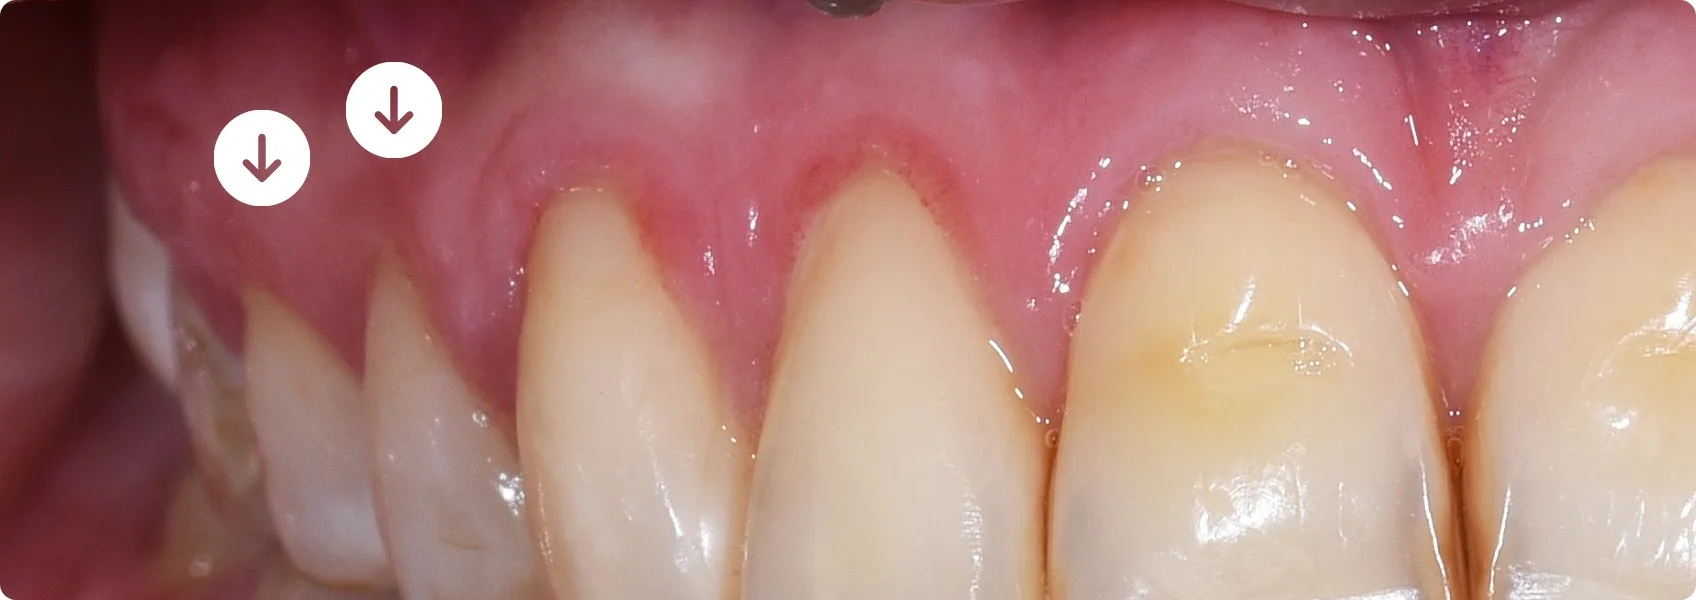

Naturalne korony przednich zębów Pacjentki były dość długie, w przeciwieństwie do tych w odcinkach bocznych. Dla podniesienia estetyki pracy doktor Ewa zaproponowała gingiwektomię — drobny zabieg korekty kształtu girlandy dziąsłowej.

Po usunięciu nadmiaru dziąsła z obu stron, zęby stały się dłuższe i bardziej proporcjonalne w stosunku do tych z przedniego odcinka.